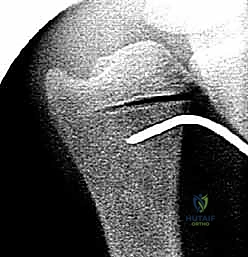

الخطوة 4: التثبيت الديناميكي (Dynamic Compression)

بعد إزالة الجزء الزائد، يتم تقريب طرفي العظم المقطوعين معاً. هنا تبرز مهارة الجراح؛ حيث يستخدم الدكتور هطيف شريحة معدنية متخصصة (Dynamic Compression Plate) ومسامير من التيتانيوم لتثبيت العظم بقوة. هذه الشريحة مصممة لضغط نهايات العظم معاً، مما يحفز الخلايا العظمية على الالتئام السريع.

الخطوة 5: التحقق بالأشعة أثناء الجراحة (Fluoroscopy)

لا يترك الدكتور هطيف شيئاً للصدفة. يتم استخدام جهاز الأشعة السينية المباشر داخل غرفة العمليات للتأكد من المحاذاة المثالية للعظم، والوضع الصحيح للشريحة والمسامير، والتأكد من استعادة التباين الزندي المحايد وحل مشكلة الانحشار تماماً.